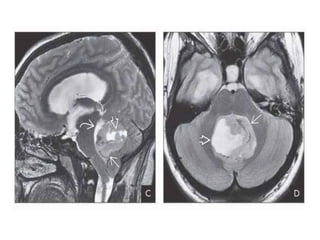

T2WI in the same patient shows mixed signal intensity in the mass. Note severe

obstructive hydrocephalus with “halo” of fluid around both temporal horns. T2* shows

“blooming” hypointensities around and within the mass, probably a combination of

hemorrhage and calcification

Sagittal T1 C+ FS scan in the same patient shows that the mass

enhances intensely. Note tumor in the anterior recesses of the third

ventricle and along the floor of the fourth ventricle . Axial T1 C+ FS

shows the enhancing mass, sulcal cisternal enhancement suggesting

DWI shows diffusion restriction. ADC map shows moderate restriction consistent with a highly

cellular mass. Germinoma